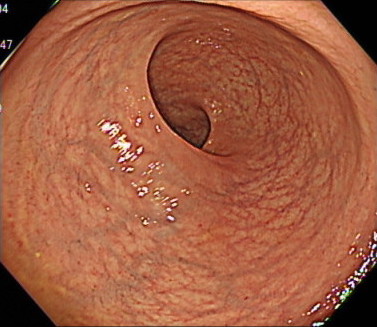

7. 先端フードを使用しないことで、広い視野を実現

「どんなに小さなポリープや変化も見逃さない」

大腸カメラでは、「先端フード」とよばれるカメラの先端につけるキャップのようなものがあります。

このキャップを内視鏡に装着することで、カメラの挿入がしやすくなるというメリットがあります。

しかし、周りの視野がせまくなるというデメリットがあります。

当クリニックでは、「軸保持短縮法」により腸に負担なくスムーズな挿入を行うことで、先端アタッチメントなしでの大腸カメラ検査を実現しています。

これにより、広い視野での大腸の観察が可能となり、どんなに小さなポリープや変化も見逃さず、早期発見・早期治療を行い、患者様に安心を提供できるよう尽力しております。

(※出血量が多い場合は、出血部位を特定しやすくするために、あらかじめ先端アタッチメントを装着して検査を行います。)

盲腸の観察(先端フードなし)